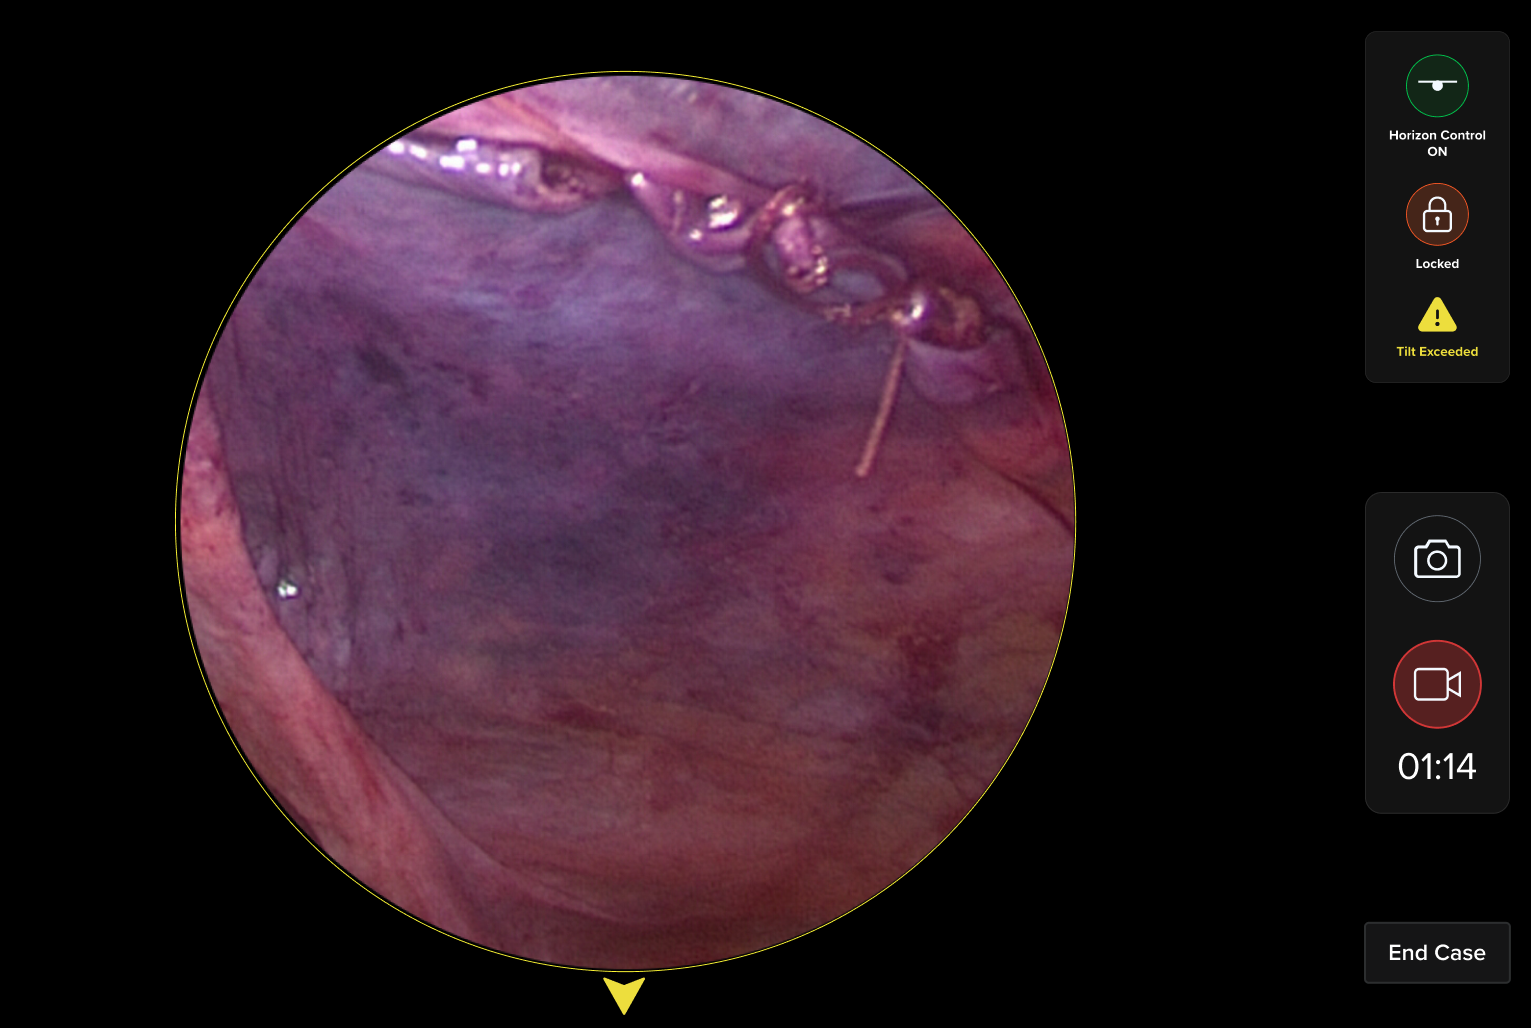

Watch how I brought digital designs to life with real medical hardware

HUD Design: Surgery-Ready Interfaces

Operating rooms aren't like offices. I designed interfaces specifically for heads-up displays, considering lighting, distance, and the critical nature of surgical procedures.